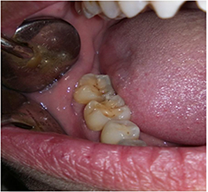

El efecto adverso difícil de manejar en la cavidad oral, es la osteonecrosis mandibular (ONM). La osteonecrosis es la muerte del hueso producido por falta de riego sanguíneo en él, produciendo la exposición del hueso en la cavidad oral. Los desencadenantes conocidos más frecuentes son la extracción o manipulación dentaria en pacientes tratados con bisfosfonatos.

Los casos graves pueden provocar la exposición y pérdida de gran parte de hueso. Dado que el fármaco causante se fija de forma casi irreversible al hueso, durante largo tiempo, la curación definitiva de la Osteonecrosis mandibular producida por bisfosfonatos es, hoy en día, improbable.